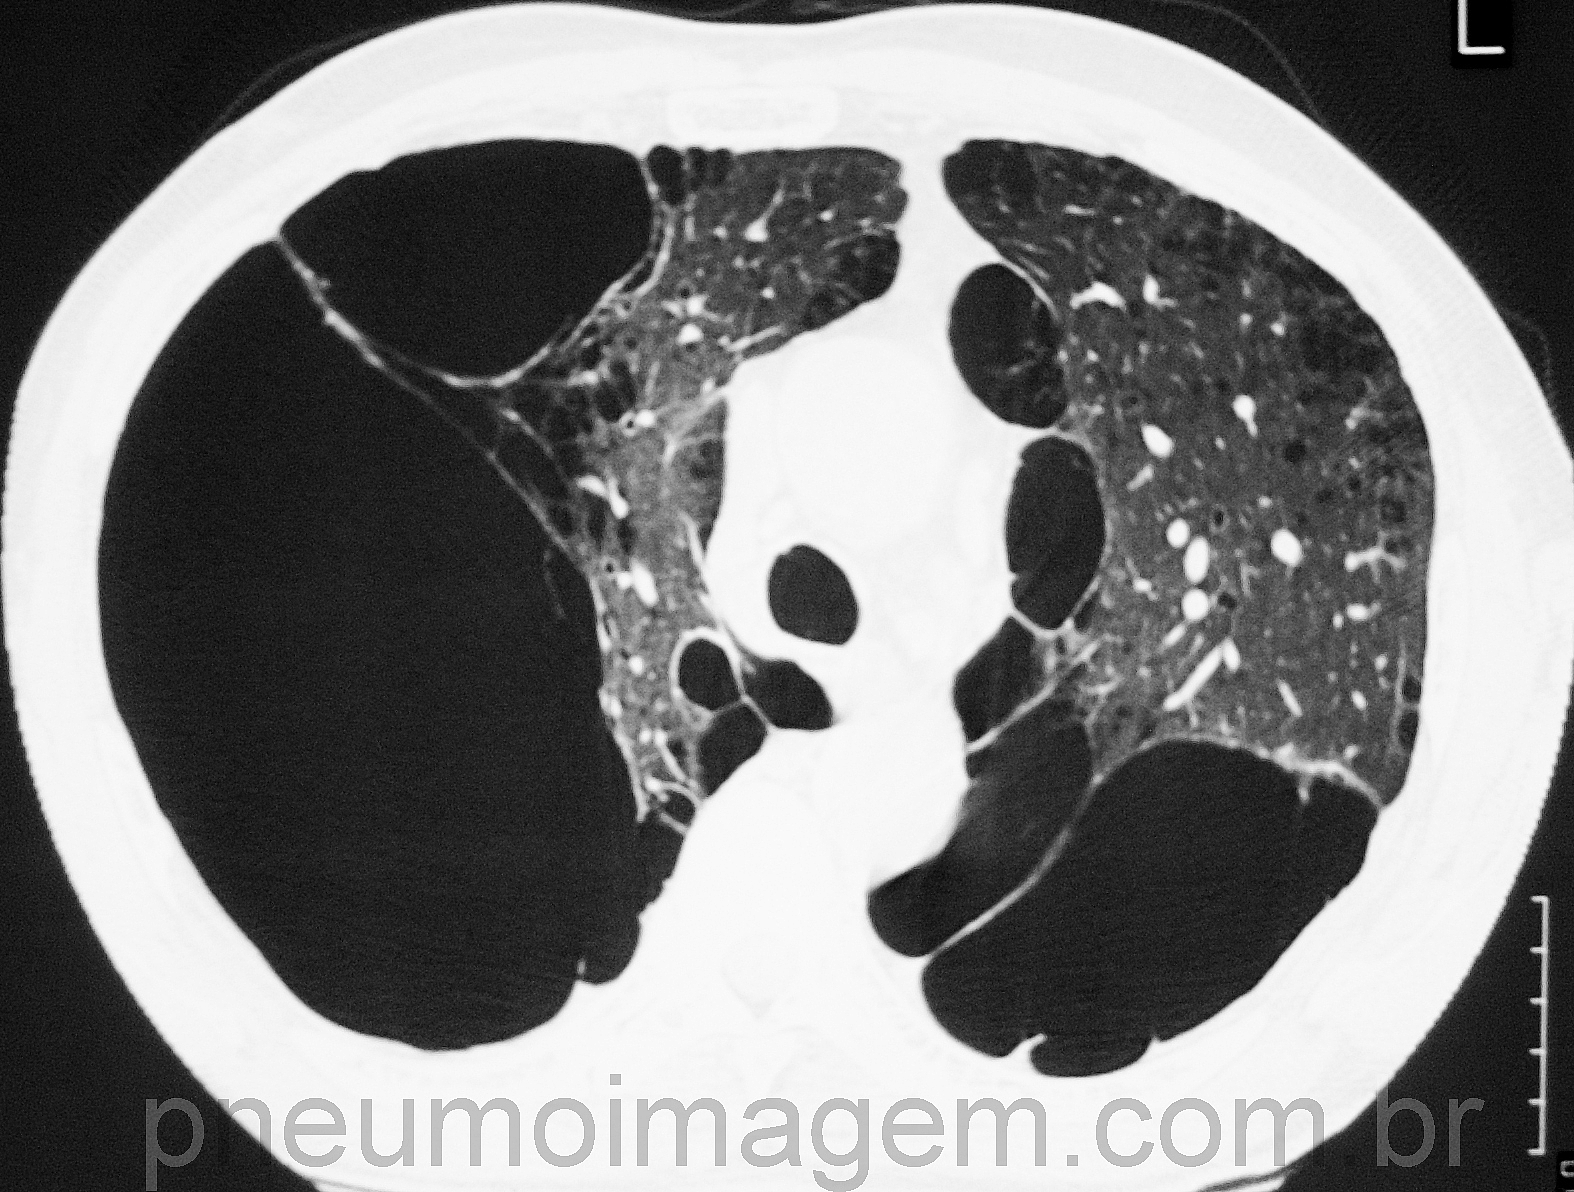

Estudo publicado no Lancet não demonstrou redução da mortalidade em pacientes com Doença Pulmonar Obstrutiva Crônica (DPOC) e risco de doença cardiovascular e que usaram o Furoato de Fluticasona (corticoide inalado), o Vilanterol (beta-agonista de longa ação) ou a combinação de ambos comparados ao placebo. Os resultados contrastam com um estudo anterior (TORCH) com drogas similares, que encontrou uma redução na mortalidade respiratória e cardiovascular com salmeterol inalado e propionato de fluticasona.

O estudo, chamado SUMMIT, foi multicêntrico, duplo-cego, randomizado e controlado. Foram avaliados 16,485 fumantes atuais ou ex-fumantes (pelo menos 10 maços-anos) ou com uma história ou um risco aumentado de doença cardiovascular. A idade variou entre 40 a 80 anos o FEV1 pós-broncodilatador entre 50% e 70% do valor previsto, com uma relação de FEV1/CVF menor que 0,7 e uma pontuação de 2 ou superior na escala de dispneia do Medical Research Council modificada. A maioria (85%) dos participantes preencheram os critérios para a classe de DPOC GOLD B.